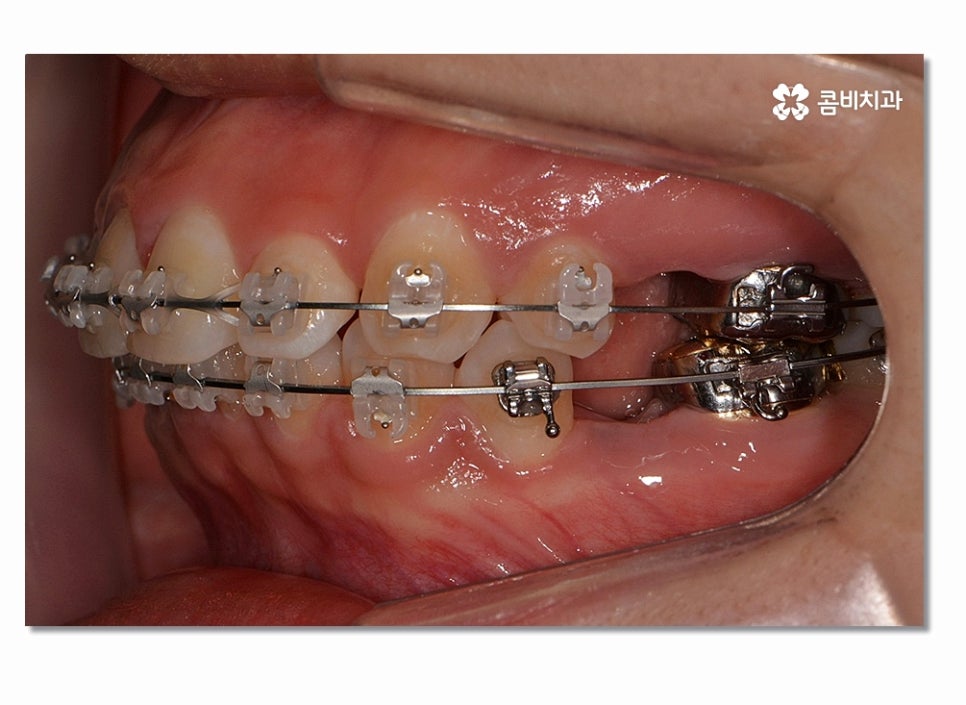

돌출입치아교정이 시작되면 이처럼 전방으로 뻐드러진

앞니를 시간이 지남에 따라서 후방으로 이동시키면서 돌출입이

점점 개선되며 이러한 치열의 변화는 교합도 잘 맞물리도록

위 사진을 보시면 치아교정 과정을 통해서 치열의 가지런함은 물론이며

측면에서 보더라도 돌출입이 많이 개선된 것을 느낄 수 있을 거예요.